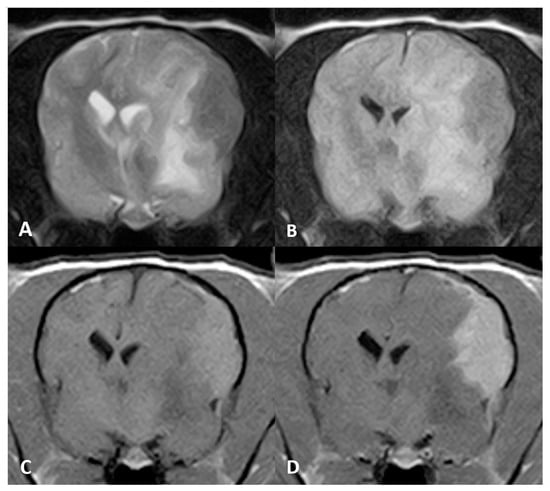

The microscopic examination of all cases revealed densely cellular, nonencapsulated, poorly delimitated neoplastic proliferations that affected the leptomeninges and infiltrated the adjacent cortical neuropil. All tumours were mainly composed of round-to-polygonal cells arranged in sheets with variable amounts of fibrovascular stroma. The cellularity displayed abundant PAS-positive eosinophilic granules within the cytoplasm. Mild pleomorphism with low mitotic count per high power field were seen in all cases. In the adjacent neuroparenchyma, moderate spongiosis and neuroinflammation could be seen. Immunohistochemical study showed consistent results in all three cases. Tumours exhibited strong positivity for ubiquitin, variable degrees of S-100 positivity and were negative for SOX-10 immunostaining (see Figure 4).

Figure 4. Macroscopic, histological and immunohistochemical features of Case 2. Caudal view of cerebral cross-sections. (A) Whitish multilobulated mass can be seen affecting the olfactory bulb with a diffuse enlargement of the left cerebral hemisphere. (B) Haematoxylin and eosin staining revealed neoplastic cells growing in sheets, with (C) a wide cytoplasm containing PAS-positive granules and (D) a strong expression of cytoplasmic ubiquitin protein. No immunoreactivity was detected against the (E) S-100 and (F) SOX-10 proteins. Positive controls of ubiquitin, S-100 and SOX-10 are shown in each inset.